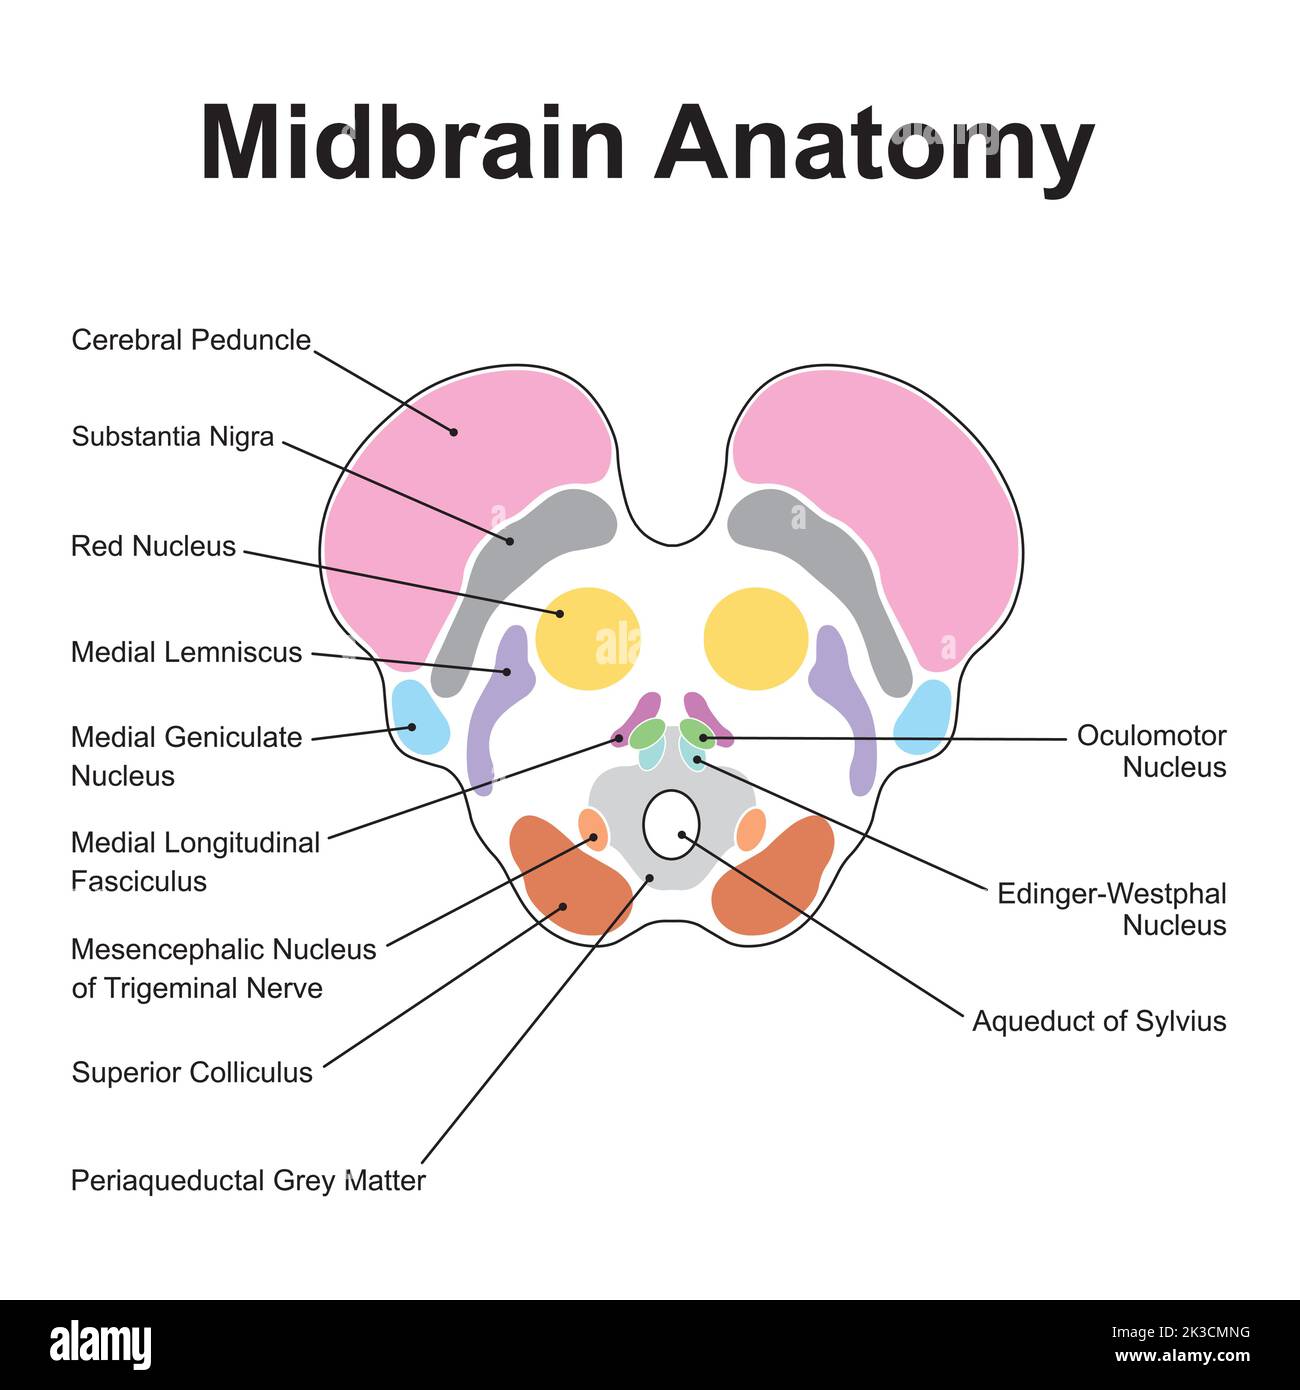

RF2K3CMNG–Wissenschaftliche Gestaltung der Anatomie des Mittelhirns. Axialer Schnitt auf der Ebene des Oberen Kollikulus. Bunte Symbole. Vektorgrafik.

RF2K3CMHJ–Wissenschaftliche Gestaltung der Anatomie des Mittelhirns. Axialer Schnitt auf der Ebene des Oberen Kollikulus. Bunte Symbole. Vektorgrafik.

RF2K3CMH3–Wissenschaftliche Gestaltung der Anatomie des Mittelhirns. Axialer Schnitt auf der Ebene des Oberen Kollikulus. Bunte Symbole. Vektorgrafik.